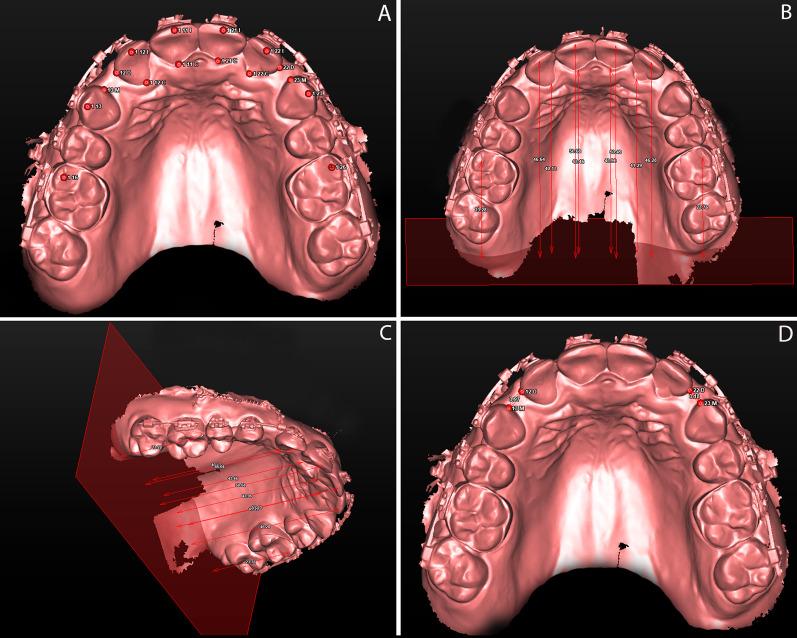

Forty-two patients aged 16-40 were recruited and randomly assigned into two groups, one which underwent MOPs (MOPG) in the buccal and palatal region of all maxillary incisors immediately before the start of retraction and one which did not (CG). Eligibility criteria included the orthodontic need for maxillary first premolars extraction and space closure in two phases. The primary outcome of the study consisted of measuring the rate of space closure and, consequently, the rate of incisors' retraction using digital model superimposition 14 days later and monthly thereafter for the next 4 months. The secondary outcomes included measuring anchorage loss, central incisors' inclination, and root length shortening, analyzed using cone beam computed tomography scans acquired before retraction and 4 months after retraction. Randomization was performed using QuickCalcs software. While clinical blinding was not possible, the image's examinator was blinded.

招募了 42 名年龄在 16-40 岁的患者,并将其随机分为两组,一组在开始内收前立即在所有上颌切牙的颊侧和腭侧进行 MOPs(MOPG),另一组不进行(CG)。入选标准包括上颌第一前磨牙拔牙和两期分阶段关闭间隙的正畸需求。研究的主要结果包括使用数字模型叠加测量 14 天后和随后每月测量 4 个月内的间隙关闭率,从而测量切牙的内收率。次要结果包括使用锥形束 CT 扫描测量支抗丢失、中切牙倾斜和根长缩短,在开始内收前和内收后 4 个月进行测量。随机化使用 QuickCalcs 软件进行。虽然无法进行临床盲法,但图像检查者是盲法的。